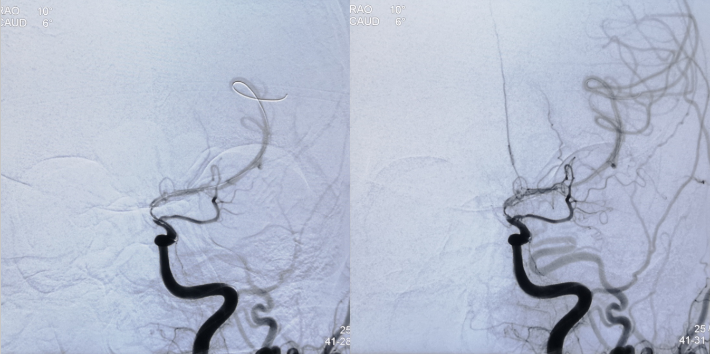

术 后

✔术中要点:左侧颈内动脉虹吸段狭窄考虑为夹层,予反复多个角度导引导管造影,以明确真假血管腔,微导丝通过狭窄段血管时谨慎、轻柔操作,务必判断导丝应从真腔通过。先予球囊扩张,观察扩张后狭窄段血管管径恢复情况。释放前准确定位支架近端,远端,应完全覆盖狭窄血管段。

✔术后处理:患者术后恢复良好,无缺血性症状及神经功能缺损体征。继续予服用双抗(阿司匹林+替格瑞洛)至少3个月。定期随访。